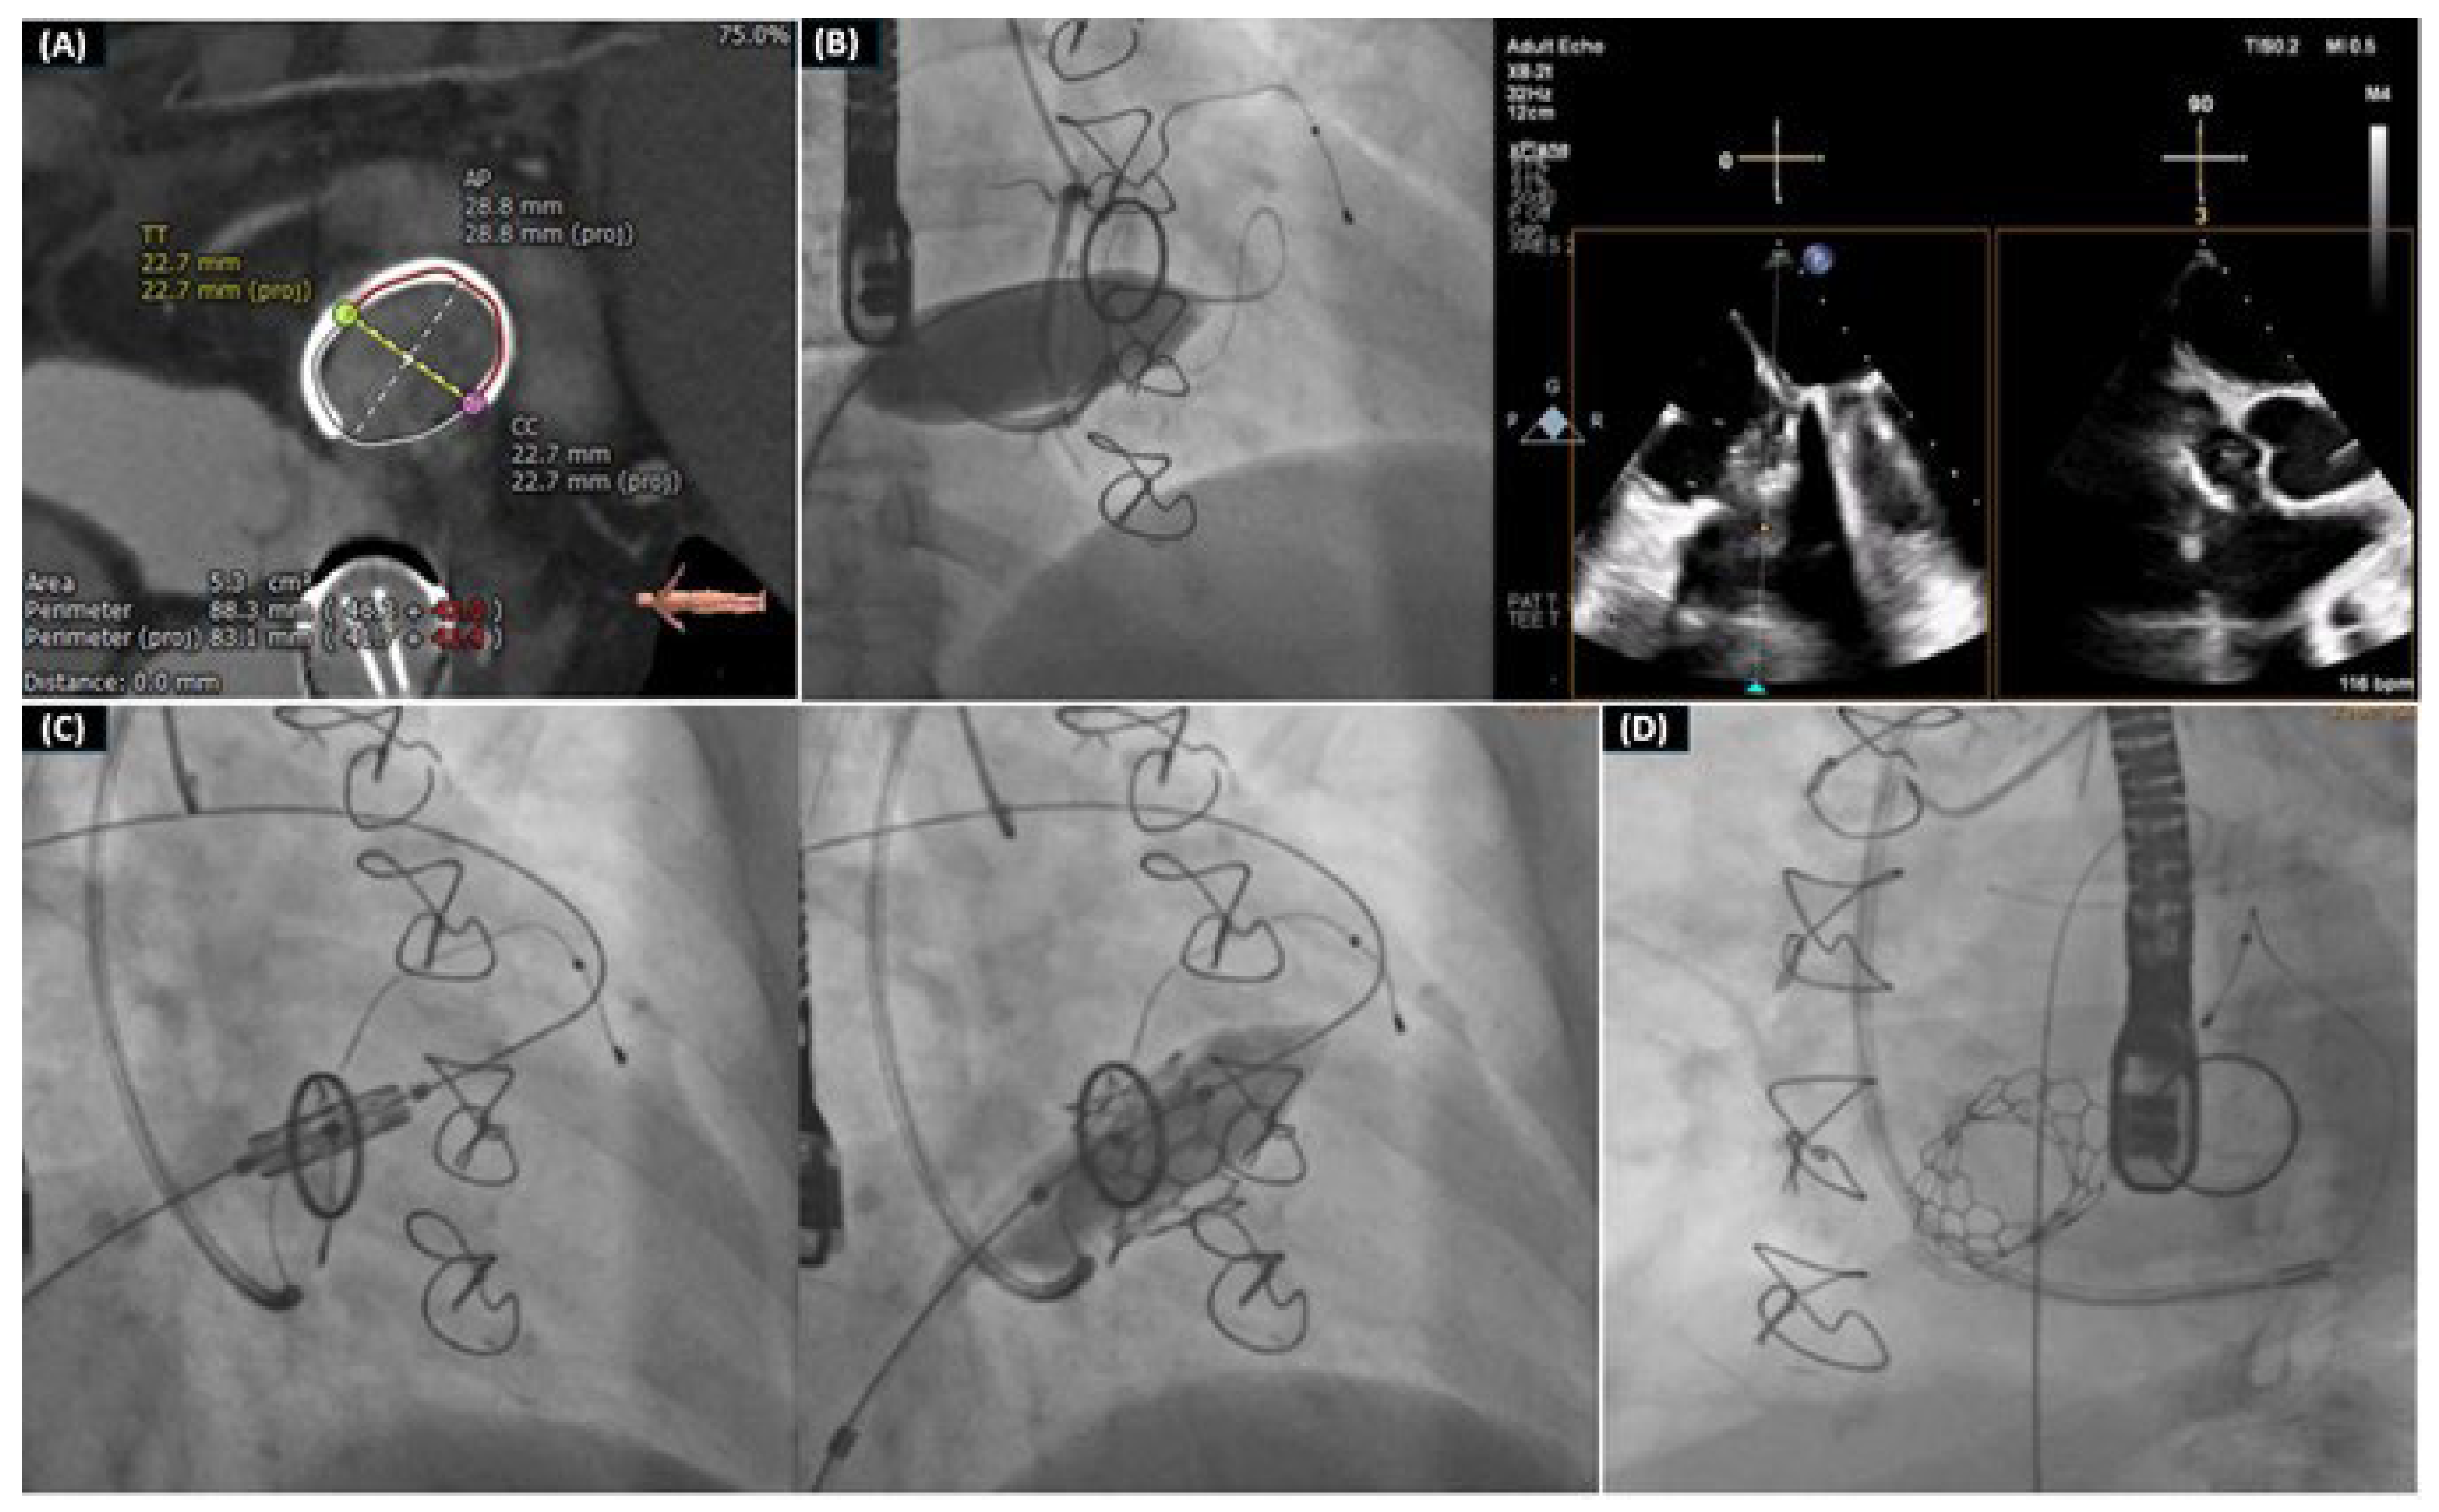

- Drakopoulou, M.; Latsios, G.; Synetos, A.; Benetos, G.; Soulaidopoulos, S.; Oikonomou, G.; Apostolos, A.; Aggeli, K.; Lozos, V.; Lymperiadis, D.; et al. Transcatheter mitral valve-in-valve replacement transeptally using a novel balloon-expandable device. J. Card. Surg. 2022, 37, 3376–3377. [Google Scholar] [CrossRef] [PubMed]

- Drakopoulou, M.; Oikonomou, G.; Latsios, G.; Synetos, A.; Benetos, G.; Simopoulou, C.; Apostolos, A.; Soulaidopoulos, S.; Aggeli, K.; Lozos, V.; et al. Takotsubo cardiomyopathy complicating transcatheter mitral valve-in-valve replacement. J. Geriatr. Cardiol. 2022, 19, 559–561. [Google Scholar] [PubMed]